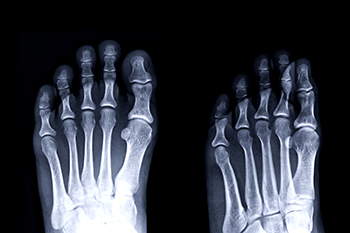

Symphalangism is a rare condition where the joints between certain bones are fused, limiting normal movement. In the feet, it often affects the toe joints, most commonly the middle joint of a toe, and results in stiffness and reduced flexibility. Causes may be genetic, as the condition is usually inherited, although it can also develop from abnormal bone growth. Symptoms include rigid toes that do not bend, discomfort while walking, difficulty finding comfortable shoes, and, in some cases, pain from pressure or altered gait. A podiatrist can help by evaluating the severity of the condition, recommending custom orthotics, providing supportive footwear advice, and offering treatment to reduce discomfort. If you have stiff or immobile toes, it is suggested that you consult a podiatrist who can accurately diagnose and offer relief solutions for what may be going on.

Rare Foot Conditions

The majority of foot conditions are common and can be treated by a podiatrist. Standard diagnostic procedures are generally used to identify specific conditions and treatment can be rendered. A podiatrist also treats rare foot conditions which can be difficult to diagnose and may need extra attention and care.

There are many rare foot conditions that can affect children. Some of these can include:

Freiberg’s disease - This can be seen as a deterioration and flattening of a metatarsal bone that exists in the ball of the foot. It typically affects pre-teen and teenage girls, but can affect anyone at any age. Symptoms that can accompany this can be swelling, stiffness, and the patient may limp.

Kohler’s disease - This often targets the bone in the arch of the foot and affects younger boys. It can lead to an interruption of the blood supply which ultimately can lead to bone deterioration. The patient may limp or experience tenderness, swelling, and redness.

Maffucci syndrome - This affects the long bones in a child’s foot leading to the development of abnormal bone lesions. They are benign growths and typically develop in early childhood and the bones may be susceptible to breaking.